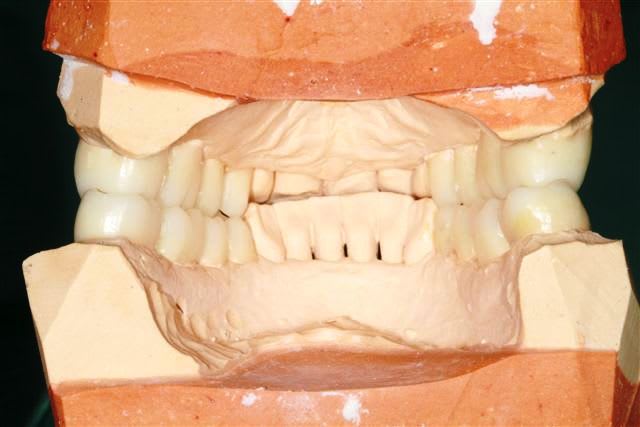

début du Waxup.

Pour les incisives du bas, je pense diminuer le bord libre.

reste à tailler le bloc antérieur.

L'avis des spécialistes en esthétique sera le bienvenu.

Les wax up sont très beaux ! j'aimerais bien que mon prothésiste me fasse des wax up bicolore comme ça...

si on veut chercher la ptite bête :

secteur gauche on a une classe 2 d'Angle molaire : donc dans l'idéal la cuspide de 25 devrait légèrement être mésialée.

Et la cuspide distale de 26 légèrement plus petite pour respecter la courbe de spee.

Mais c'est vraiment pour chercher la petite bête.

Merci pour les waxups, j'ai fait la mise en place et Brigitte la finition.

Pour la couleur, c'est un peu un hasard, mais c'est vrai qu'en photo ça rend bien.

Pour 25/26 c'est exact et la cuspide distale de 47 remonte trop...

pardon pxav , mais tes waxups , ça va pas du tout !

il faut vestibuler le haut considerablement et meme un peu le bas .tout est verouillé pire qu'avant .il faudrait sortir les cuspides vest d'au moins 2 mm minimum .donner un peu d'air en decalage lateral immediat .

je n'ai pas l'impression que les modeles soient en centrée .

je ne comprend l'interet du wax up a cette etape du cas !!!